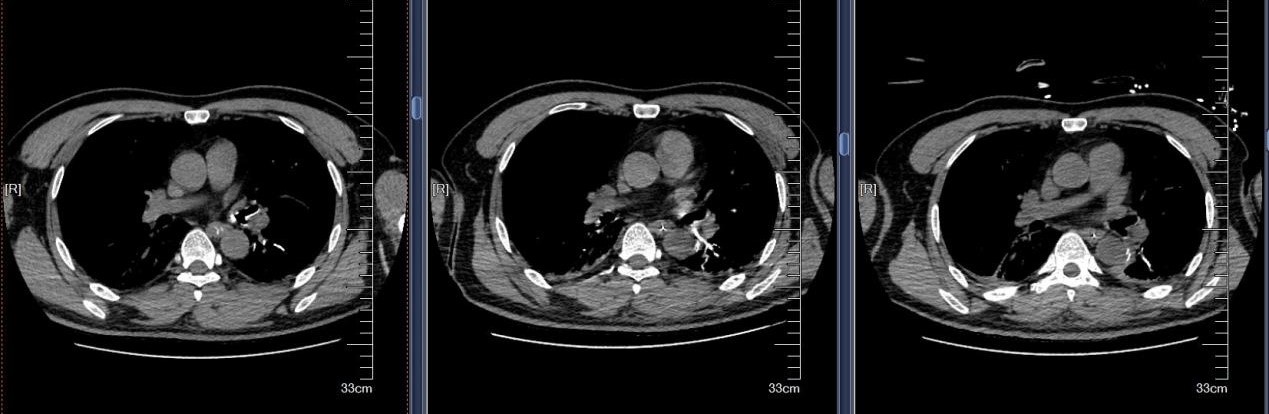

近日,苏州大学附属第四医院成功救治一例极其罕见的支气管异物危机案例。患者是一名48岁男性,因全身被水泥覆盖,伴有意识不清、呼吸困难等危急症状。紧急送医至我院后,CT检查发现其气管和双侧主支气管内充满大量高密度泥沙状异物,同时伴有多发肋骨骨折及腰椎骨折等严重外伤。面对如此复杂的病情,苏大附四院呼吸与危重症医学科蒋军红主任率领团队迅速制定了精准救治方案,成功挽救患者生命。

水泥作为化学性异物,除了造成机械性呼吸道阻塞,还会引发严重的化学性肺炎和呼吸衰竭。患者到院时已出现意识不清、呼吸困难等危重症状,气道清理成为抢救的首要目标。我院蒋军红主任凭借丰富的临床经验和技术优势,带领团队展开了一场与时间竞速的生命营救。